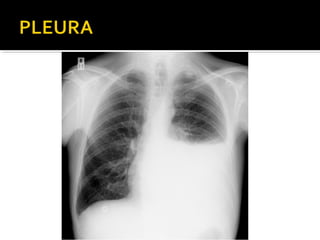

Este documento fornece parâmetros técnicos para realizar uma radiografia de tórax, incluindo posicionamento correto do paciente, dose adequada de radiação e estruturas anatômicas a serem avaliadas, como coração, pulmões, pleura, diafragma e ossos do tórax.